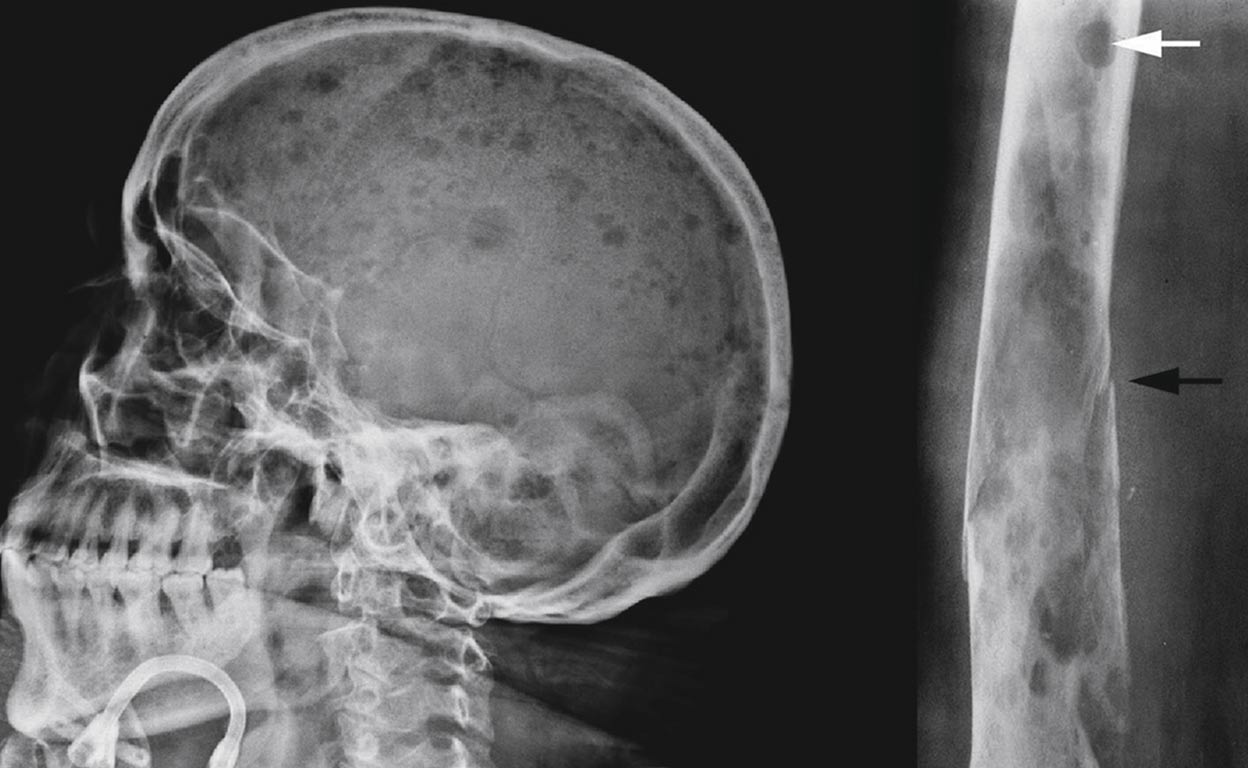

El mieloma es un cáncer de la médula ósea que acaba ‘comiéndose’ los huesos. Es difícil de diagnosticar.

La enfermedad deteriora los huesos por el mal funcionamiento de las células plasmáticas de la médula

Uno de los problemas anímicos de este cáncer es el hecho de que se pase por varios periodos de remisión y recaída. El temor a su reaparición tiñe de angustia la vida de los pacientes. Además, lógicamente, del difícil día a día, en el que la debilidad ósea puede hacer que te rompas el brazo con solo abrir una puerta.